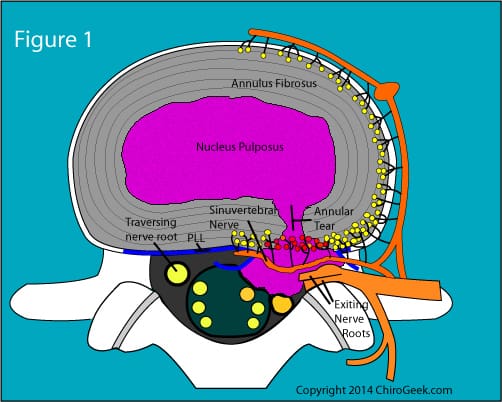

Disc protrusion refers to a condition in which the intervertebral discs, which act as cushions between the vertebrae in the spine, become compressed and bulge outwards. This can occur due to various factors, such as age-related degeneration, spinal injuries, poor posture, or repetitive strain on the spine.

Diagnostic Imaging

Imaging techniques such as X-rays, MRI, or CT scans provide detailed visuals of the spine, allowing for the identification of abnormalities like disc protrusion. These diagnostic tools can offer valuable insights into the extent of the condition and guide treatment decisions.